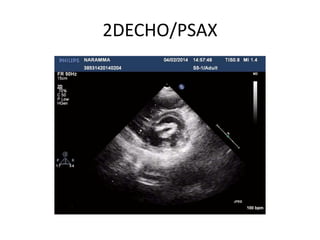

2DECHO/PSAX

PLANIMETRYPLANIMETRY

• Best correlation with

anatomical area

• Scanning method to

avoid overestimation

• measured at leaflet tips

in a plane perpendicular

to mitral orifice

• Elliptical in shape

• Direct measure of mitral

orifice including opened

commissures in PSAX